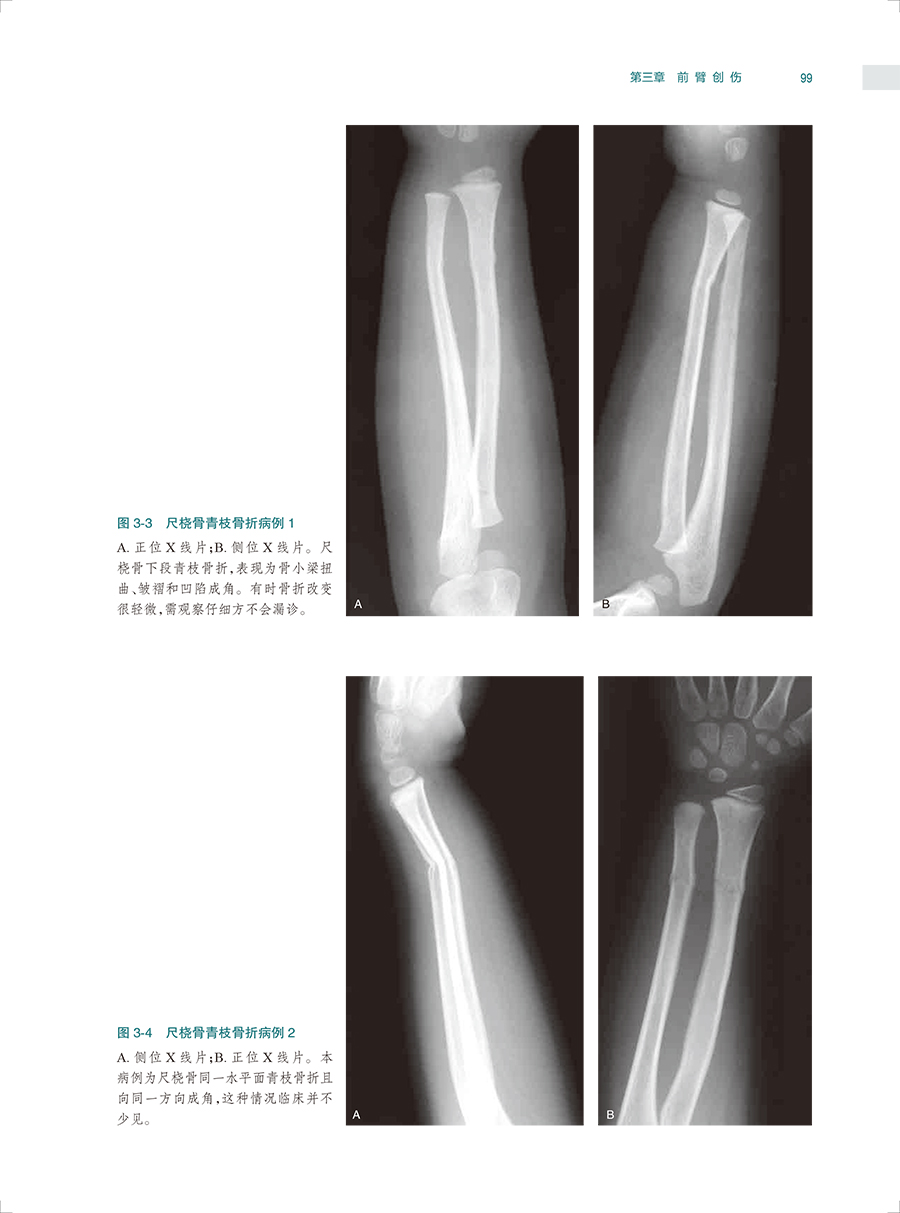

本书是一本系统全面介绍骨关节创伤X线诊断的图谱专著。全书共十六章,前十五章每章基本按创伤类型、诊断要点和鉴别诊断体例编写,最后一章介绍常见骨关节创伤后遗症及并发症。书中共选用1270幅X线照片图,约760个病例,所选图片和病例均具有代表性,可使读者对各部位、各类型的骨关节创伤及其后遗症和并发症有进一步认识,从而提高诊断水平。本书主要供骨科医生、影像科医生使用。